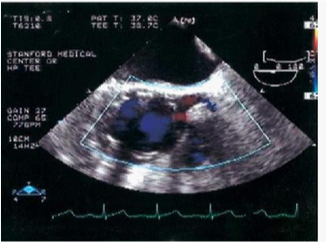

Figure 8 Ascending aorta/aortic root. The image shows the position of the graft and the patency of the left main coronary artery after the deployment of the graft.29

Figure 9 (C) Image showing active bleeding from the aortic lumen into the hematoma (arrow). (E) TEVAR showing elimination of flow.30

In contrast, Echo Doppler has been recognized as a good option to these techniques due to its low cost, easy implementation and interpretation and the absence of exposure to any type of radiation.26 This provides a better understanding of the endoleak formation mechanism and provides a more accurate analysis thereof, due to a collateral circulation. The origins of an endoleak may also be correctly identified. Compounded by the fact that it allows visualize blood flow in the aneurysm sac and its direction. This seems to be an excellent tool in the evaluation of high flow endoleaks within the aneurysmal sac. It is an imaging technique commonly used in vascular studies, being easy to perform, inexpensive, portable, secure and highly available. Its use for patients’ follow-up can reduce the biological hazards associated with CT angiography, since this frees the body of the individual to a substantial dose of ionizing radiation. The advantage of Doppler ultrasound in patients’ follow-up with aortic stent graft is that it allows a serial measurement over time of the residual diameter of the aorticaneurysm sac. Doppler ultrasound is more accurate than CT for the detection of problems associated with stent graft patency, their migration, kinking and stenosis. Provides physiological and anatomical information at the same time, unlike CT. The ability to quantify and compare serial images at a low cost without contrast and radiation, suggests that this technique should be the Gold Standard in the follow-up to TEVAR (Figures 5-9).20,24,27